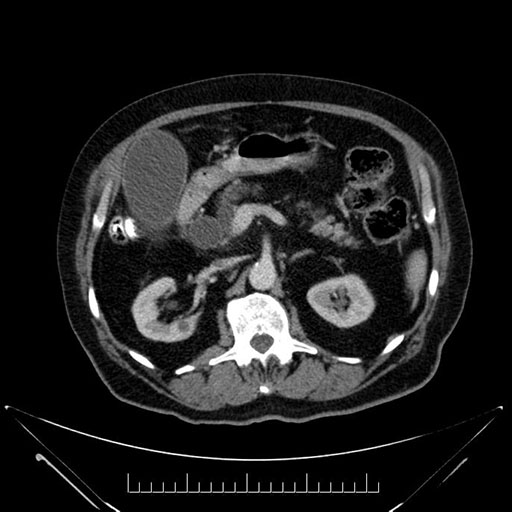

Imaging Analysis

Look through the patient's CT scan to identify any areas of concern for the necessary procedure.

Based on your CT findings, which issue(s) would give reason for "planned slowing down moment(s)" in this case?